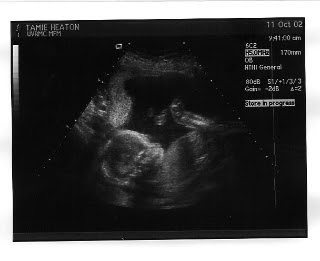

We got to see the new baby on Friday! So, the picture says it all:

It was so much fun. He was such a little cutie. We got to see his little toes (Ryan thinks the feet are the best part of the baby), his heart, and how he moved around in Tamie's tummy.

We actually didn't find out the gender at the ultrasound, but we had them write it down on a little card and put it in an envelope, like Juliet and Rob. We went to the temple later that day and opened it the celestial room. It was a beautiful day. However, for any of you who are thinking about doing it the say way, make sure you break the seal on the envelope before you get to the celestial room. Tearing it open when everything was silent turned out to be somewhat loud.